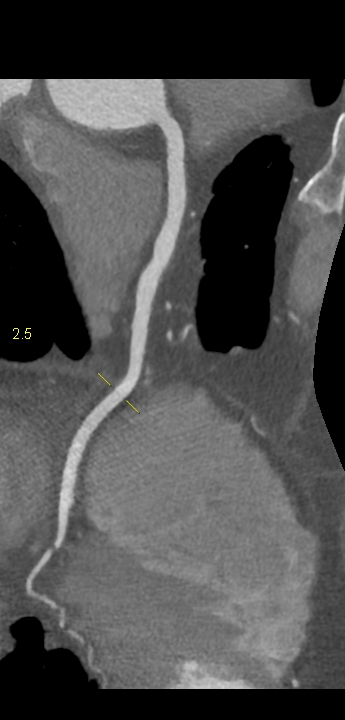

Figururile 1-9: reconstrucție în axul lung al vasului pentru arterele coronare cu evidențierea unui calibru global crescut la nivelul acestora și cu încărcătură ușoară-moderată de placă în principal calcificată

Discuţie caz nr 132: Examinările coroCT se efectuează în principal pentru aprecierea încărcăturii de placă precum și pentru evidențierea reducerilor de lumen ce necesită tratament. Această examinare a evidențiat creștere globală a calibrului arterelor coronare și o încărcătură ușoară-moderată cu placă în principal calcificată, fără a se evidenția arii de stenoză.

DE LUAT ACASĂ!!! Ectazia coronariană este o afecțiune rară caracterizată prin dilatarea anormală (diametrul vasului este de 1.5 ori mai mare) a arterelor coronare, care poate duce la afectarea fluxului sanguin și la un risc crescut de ischemie. Etiologia nu este cunoscută iar afecțiunea poate fi asociată cu ateroscleroză sau factori congenitali și reprezintă o provocare atât în diagnostic, cât și în tratament. Simptomele se suprapun adesea cu cele ale altor boli coronariene, ceea ce face ca identificarea timpurie să fie crucială. Opțiunile de tratament variază de la tratamentul medical cu terapie antiplachetară sau anticoagulantă până la proceduri intervenționale, cum ar fi angioplastia sau intervenția chirurgicală, în funcție de severitatea și riscul de complicații. Tratamentul pe termen lung se concentrează pe prevenirea evenimentelor ischemice și pe abordarea cauzelor care stau la baza acestora.